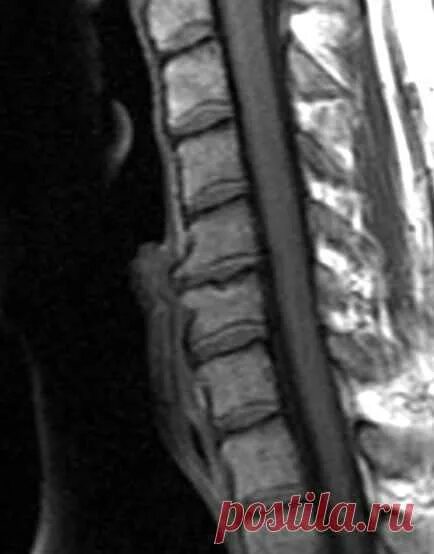

Дегенеративно дистрофические изменения дисков l5 s1